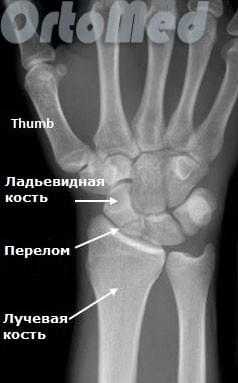

Функция пальцев полная. Сила кулачного схвата правой (доминантной) кисти — 22 кг, снижена почти в 2 раза по сравнению с нормой. Сила схвата левой кисти — 40 кг. Оценка по шкале ВАШ — 3 балла, по опроснику DASH — 21,16 балла. На рентгенограмме (рис. 5, а, б, в) и при компьютерной томографии выявлен ложный сустав ладьевидной кости (см. рис. 6, г). Рис. 6. Пациент К., 19 лет. Диагноз: ложный сустав ладьевидной кости правой кисти. а — рентгенограмма в прямой проекции; б — рентгенограмма в ¾; в — рентгенограмма в боковой проекции; г — компьютерная томография.

Первым и обязательным диагностическим моментом является рентгенография поврежденного участка конечности. Чаще всего рентгенография ясно показывает характер перелома ладьевидной кости.

В некоторых случаях, когда по рентгенограмме тяжело определить соотношение отломков назначается компьютерная томография лучезапястного сустава. При таком исследовании можно трехмерно увидеть поврежденную кость, что поможет в определении тактики оперативного лечения перелома.

Начинать диагностику лучше всего с осмотра у врача, при подозрении на травму запястья делают рентгенограммы лучезапястного сустава. Важно сделать помимо стандартных прямой и боковой проекций еще и дополнительную косую, в которой лучше всего будет видна ладьевидная кость. Бывает так, что на первичных рентгенограммах перелом не выявляется. При сохранении симптоматики и отсутствии признаков костной травмы на рентгене следует повторить исследование через неделю или сделать компьютерную томографию (КТ) для уверенного подтверждения или исключения перелома.

Схематичное изображение и рентгенограмма перелома ладьевидной кости в области ее «талии». Это наиболее частая локализация перелома.